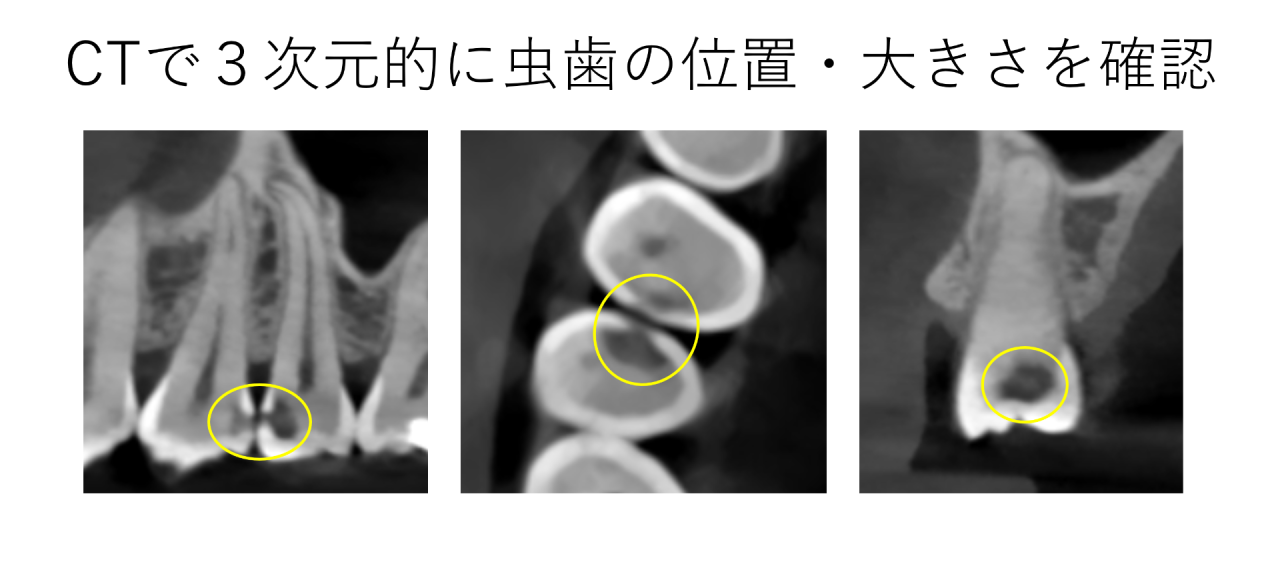

患者様の歯を検査すると、歯と歯の間に虫歯の穴を発見しました。穴自体は小さいものですが、虫歯にはアリの巣のような特徴があり、入り口は小さく、歯の中で大きく広がります。通常のレントゲンではその広がり方が不明瞭のため、CTを撮影しました。

CTで確認すると、どちらも大きく歯の中で広がっており、特に後ろの歯が神経に半分近く迫るくらいになっていました。この大きさであれば、お口の中できれいにつめ物をすることは難しく、歯型を取り銀歯やセラミックのつめ物を行うのが一般的です。